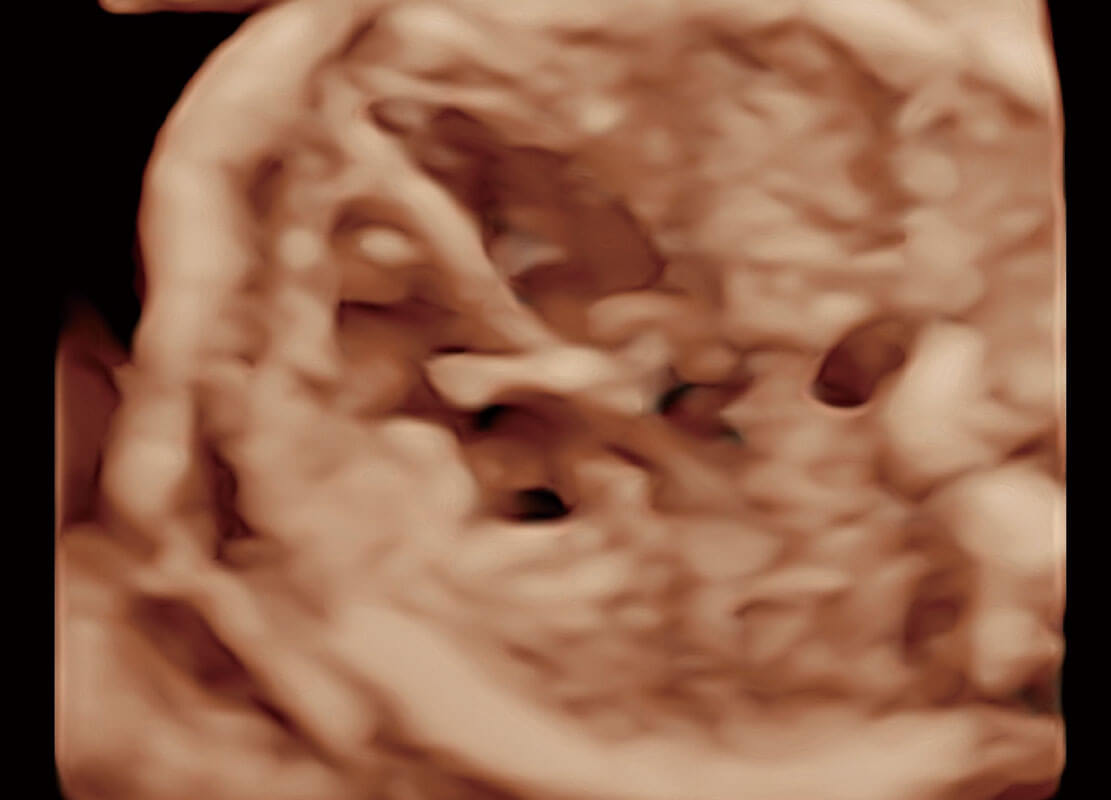

P60搭载一系列胎儿心脏成像技术,实现精细的胎儿心脏评估。

• 四腔切面

• 四腔心血流

• 右室双出口

• 胎心容积成像